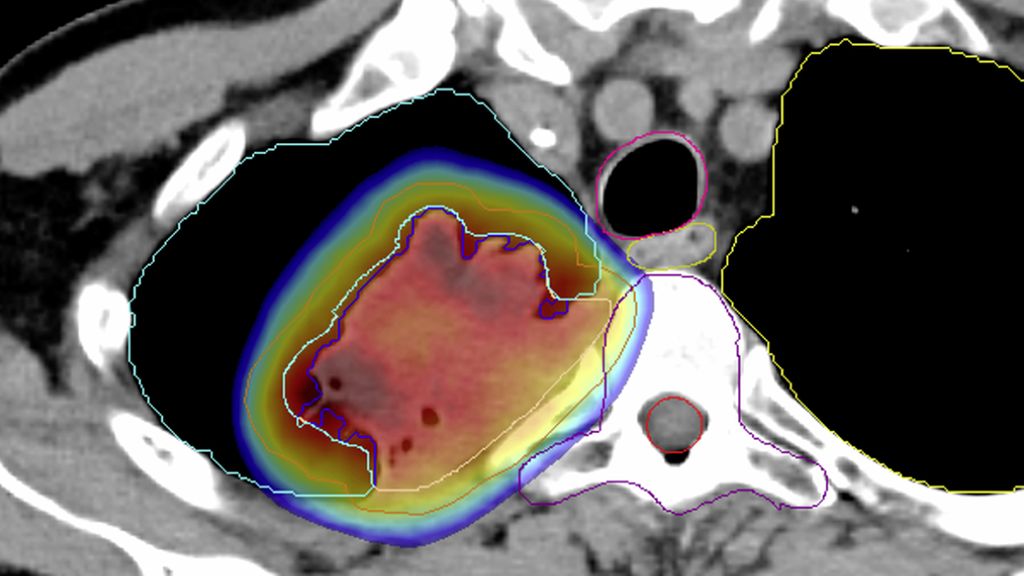

Auch die Rolle der Strahlentherapie im perioperativen Setting ist im Zeitalter der Immuntherapie erneut Gegenstand der Forschung. Aktuell untersucht die Schweizer Studie SAKK 16/18, ob eine Bestrahlung des Primärtumors das PFS nach neoadjuvanter Chemoimmuntherapie bei resektablem NSCLC im Stadium IIIA(N2) im Vergleich zur Vorgängerstudie SAKK 16/14 weiter verbessern kann.20 Die Strahlentherapie erfolgt parallel zur neoadjuvanten Immuntherapie unter Aussparung des Mediastinums, um Toxizität und immunsuppressive Effekte zu vermeiden (Abb. 2). Speziell ist zudem, dass drei unterschiedliche Strahlentherapiekonzepte randomisiert untersucht werden, um mögliche Unterschiede im Synergismus mit der Immuntherapie zu untersuchen. Interimdaten bestätigen die Sicherheit dieses Ansatzes, für den eine kleinere Studie aus China in ähnlicher Form kürzlich eine sehr hohe Rate an pathologischer Remission (MPR) von 76% präsentieren konnte.21,22

Abb. 2: Immunmodulatorische Strahlentherapie in der SAKK 16/18-Studie: Die Studie untersucht, ob eine Bestrahlung die Wirkung der Immuntherapie mit Durvalumab im neoadjuvanten Setting verbessern kann. Die Strahlentherapie erfolgt fokussiert auf den Primärtumor, wobei Normalgewebe sowie Lymphknoten im Mediastinum geschont werden. Darstellung: PET-CT (links); Strahlentherapie-Plan (rechts), Farbverlauf mit Dosis ≥20Gy im Arm B (5x5Gy). Quelle: Universitätsspital Basel (mit freundlicher Genehmigung des Patienten)